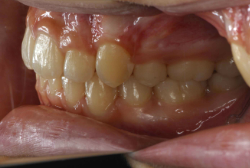

叢生(そうせい)

凸凹な歯並びのことを叢生といいます。矯正歯科に来院する患者様の主訴の中で、最も多いのが「配列の凸凹を真っ直ぐにしたい」というものです。歯の大きさと顎の大きさの調和がとれていないことが原因です。

凸凹を主体としたケースの場合、当院の平均治療期間は18ヶ月ですので、このケースは少し長めに経過しました。理由の一つは凸凹の程度がかなり重症だったと言うことですが、もう一つは、右下第2大臼歯が45度くらい前傾していたため、それを整直化させるために時間を要したと考えています。いずれにしても最終結果は大変よい状態と思います。

治療前は並びが乱れて見た目が悪いというのはもちろん問題ですが、歯科医学的に一番困るのは噛み合わせが悪いという点です。上下の犬歯(3番目の歯)は、上下的に離れた位置にあるため接触することができません。つまり歯としては存在していても、歯としては機能していないということです。